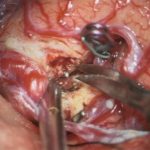

手術写真

手術前

手術中

手術後